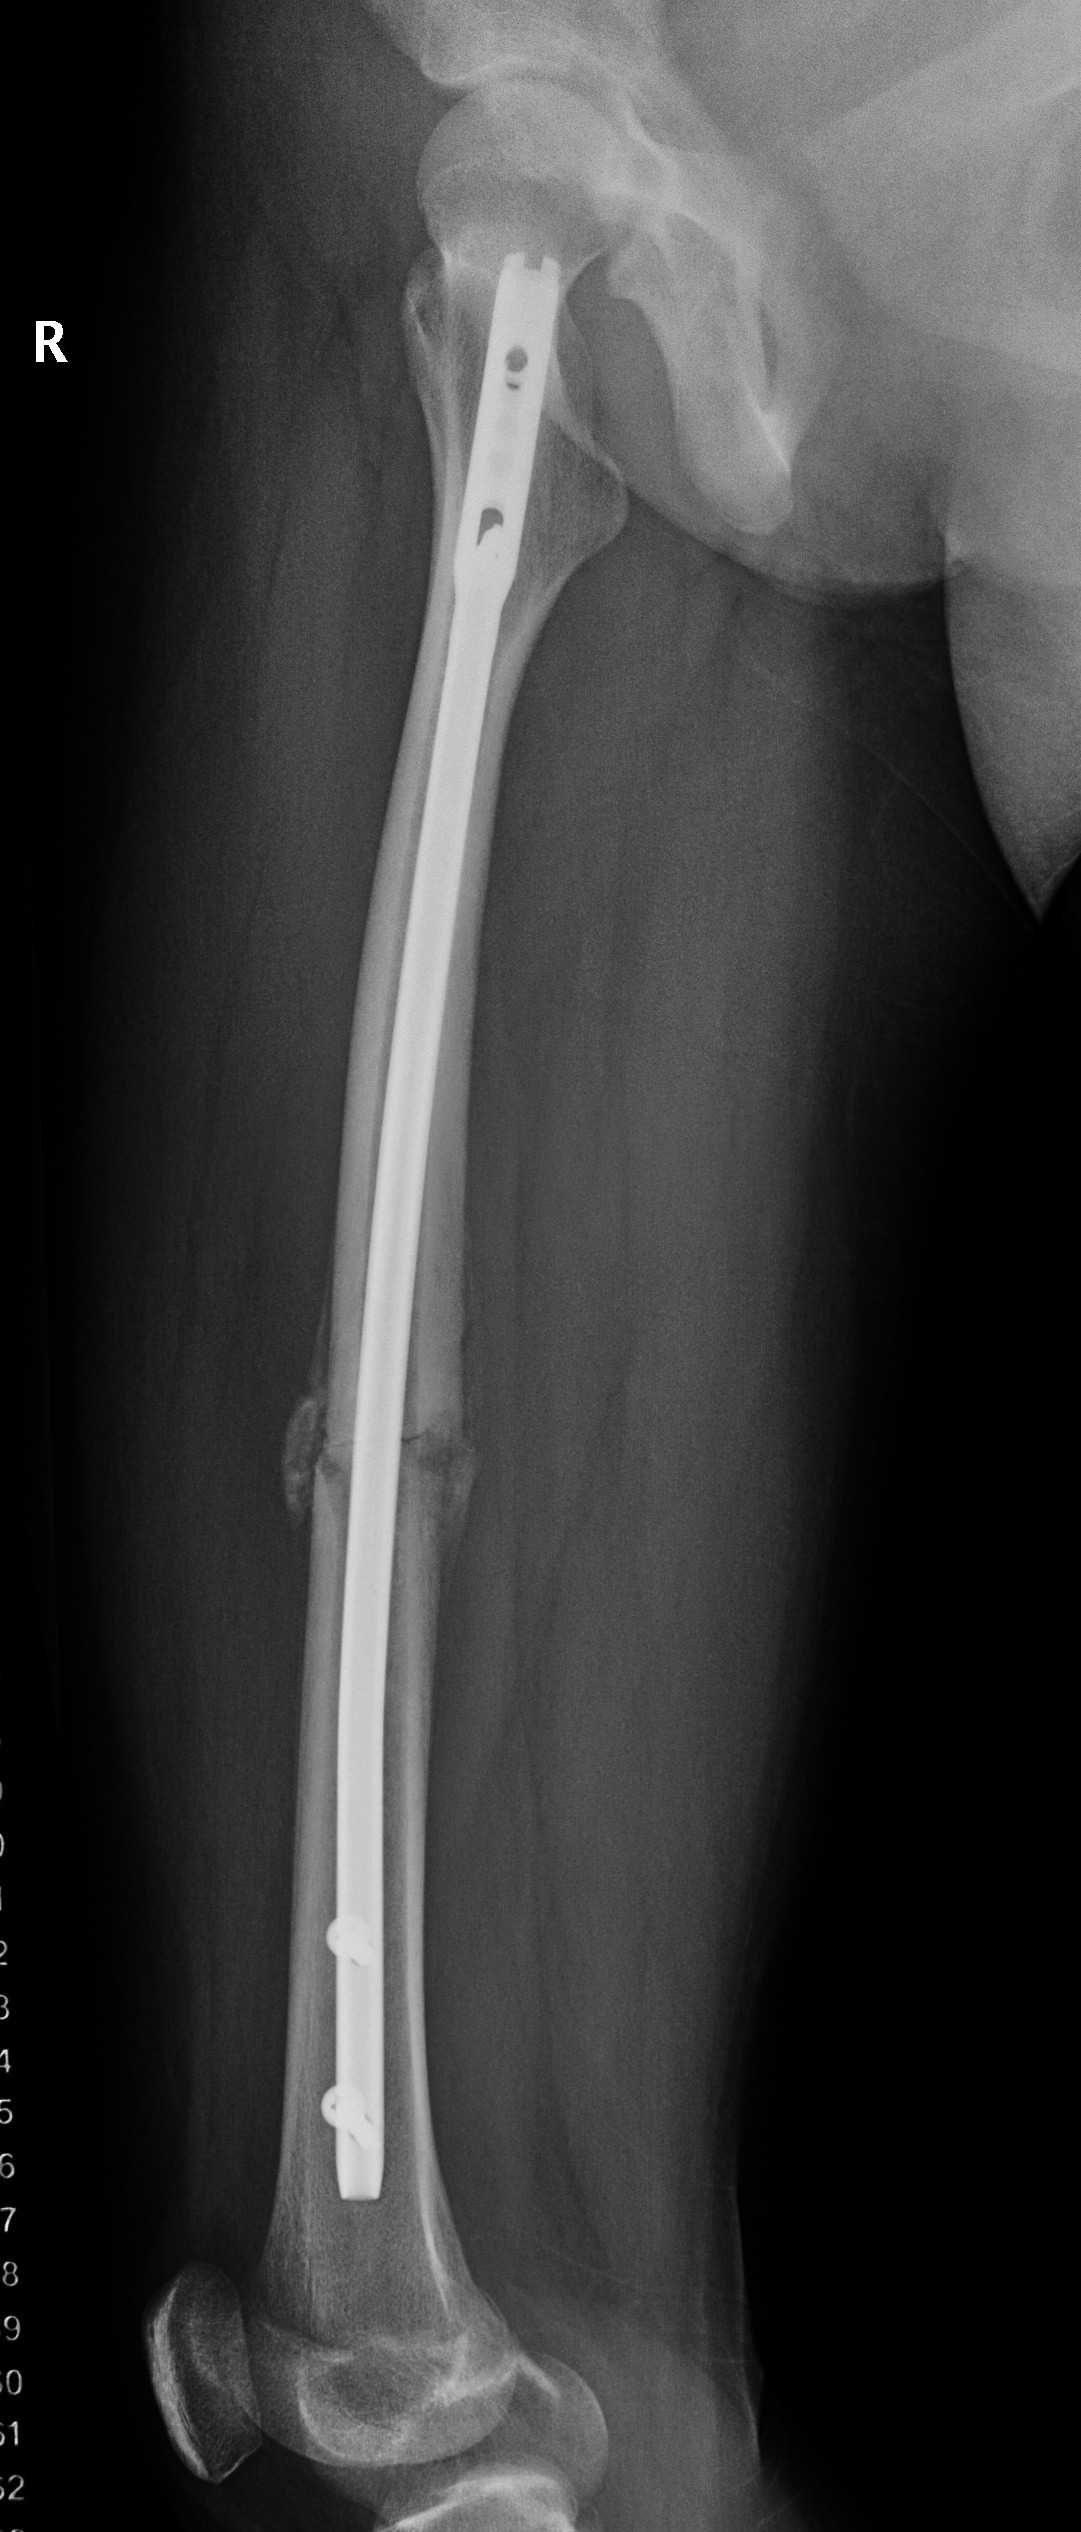

Flexible nails / Titantium Elastic Nails

Indications

Length stable fractures i.e simple transverse, short oblique

Midshaft fractures

Maximum weight up to 50 kg / 12 years old

Flexible nail technique

Wires

- available 1. 5 mm - 4.0 mm

- 30 - 40% of diameter of diaphyseal medullary canal

- i.e. if canal 10 mm wide, use 2 x 4 mm

- recommend using 2 wires same diameter to avoid rotational instability

Entry points

- medial and lateral insertion

- 1 - 2 cm proximal to distal femoral physis

Wire passage

- bend wire for 3 point fixation with bend at fracture site

- also bend the tip of the wire

- medial entry wire will pass into femoral neck

- lateral wire will pass into greater trochanter / medial wire into femoral neck

Acceptable alignment

- 10o varus / valgus

- 15o flexion / extension

- 15 mm shortening

Complications

- 234 femur fractures treated with flexible nails

- age > 11 and weight > 50 associated with poorer outcomes

- age < 11 good outcome 72%, age > 11 good outcome 55%

- leg length discrepancy and angulation associated with poorer outcomes